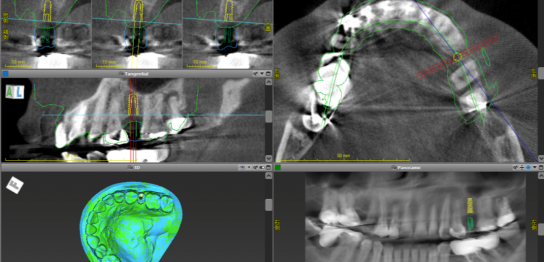

インプラントのご提案 当院の治療のこだわり 身体への負担を最小限に: 「1回の手